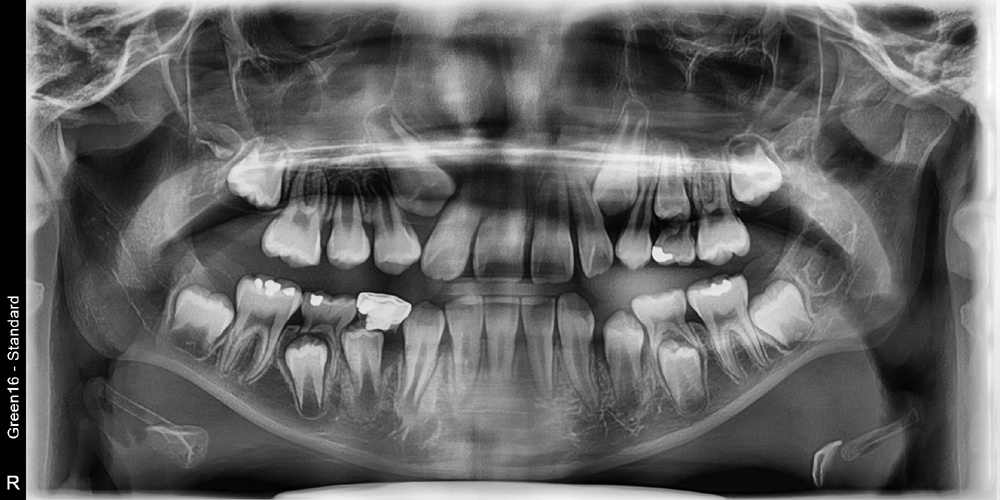

치료 전 사진입니다.